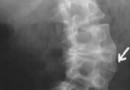

輔助檢查:拍CT,驗血